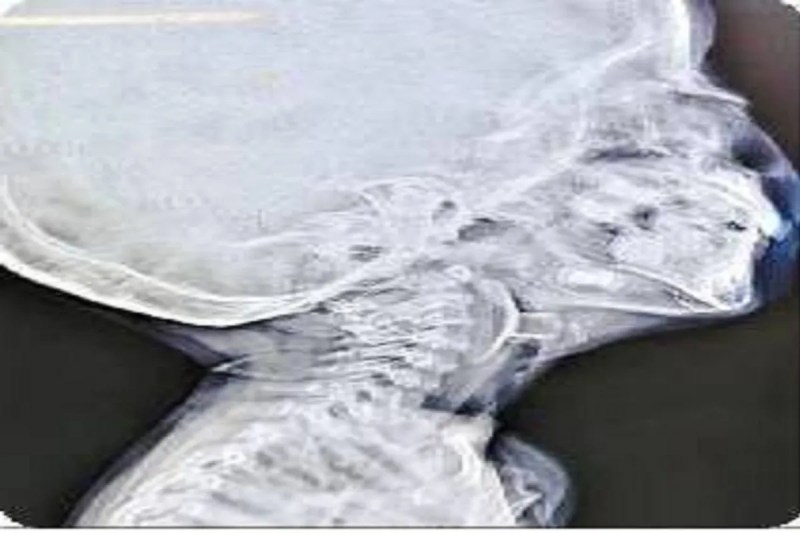

वोकल कॉर्ड में खिलौना फंसने से रुक गई थी सांस (Photo Patrika)

आपातकालीन विभाग में जांच के दौरान डॉक्टरों ने पाया कि बच्चे के श्वसन मार्ग में सक्शन कप एरोहेड टिप (जो आमतौर पर तीर-कमान सेट खिलौने का हिस्सा होती है) फंसी हुई है। यह वस्तु बच्चे की जान के लिए सीधा खतरा बन चुकी थी। तुरंत उसे पीडियाट्रिक आईसीयू में भर्ती कर स्थिर किया गया और फिर ईएनटी आपातकालीन ऑपरेशन थिएटर में ले जाया गया।